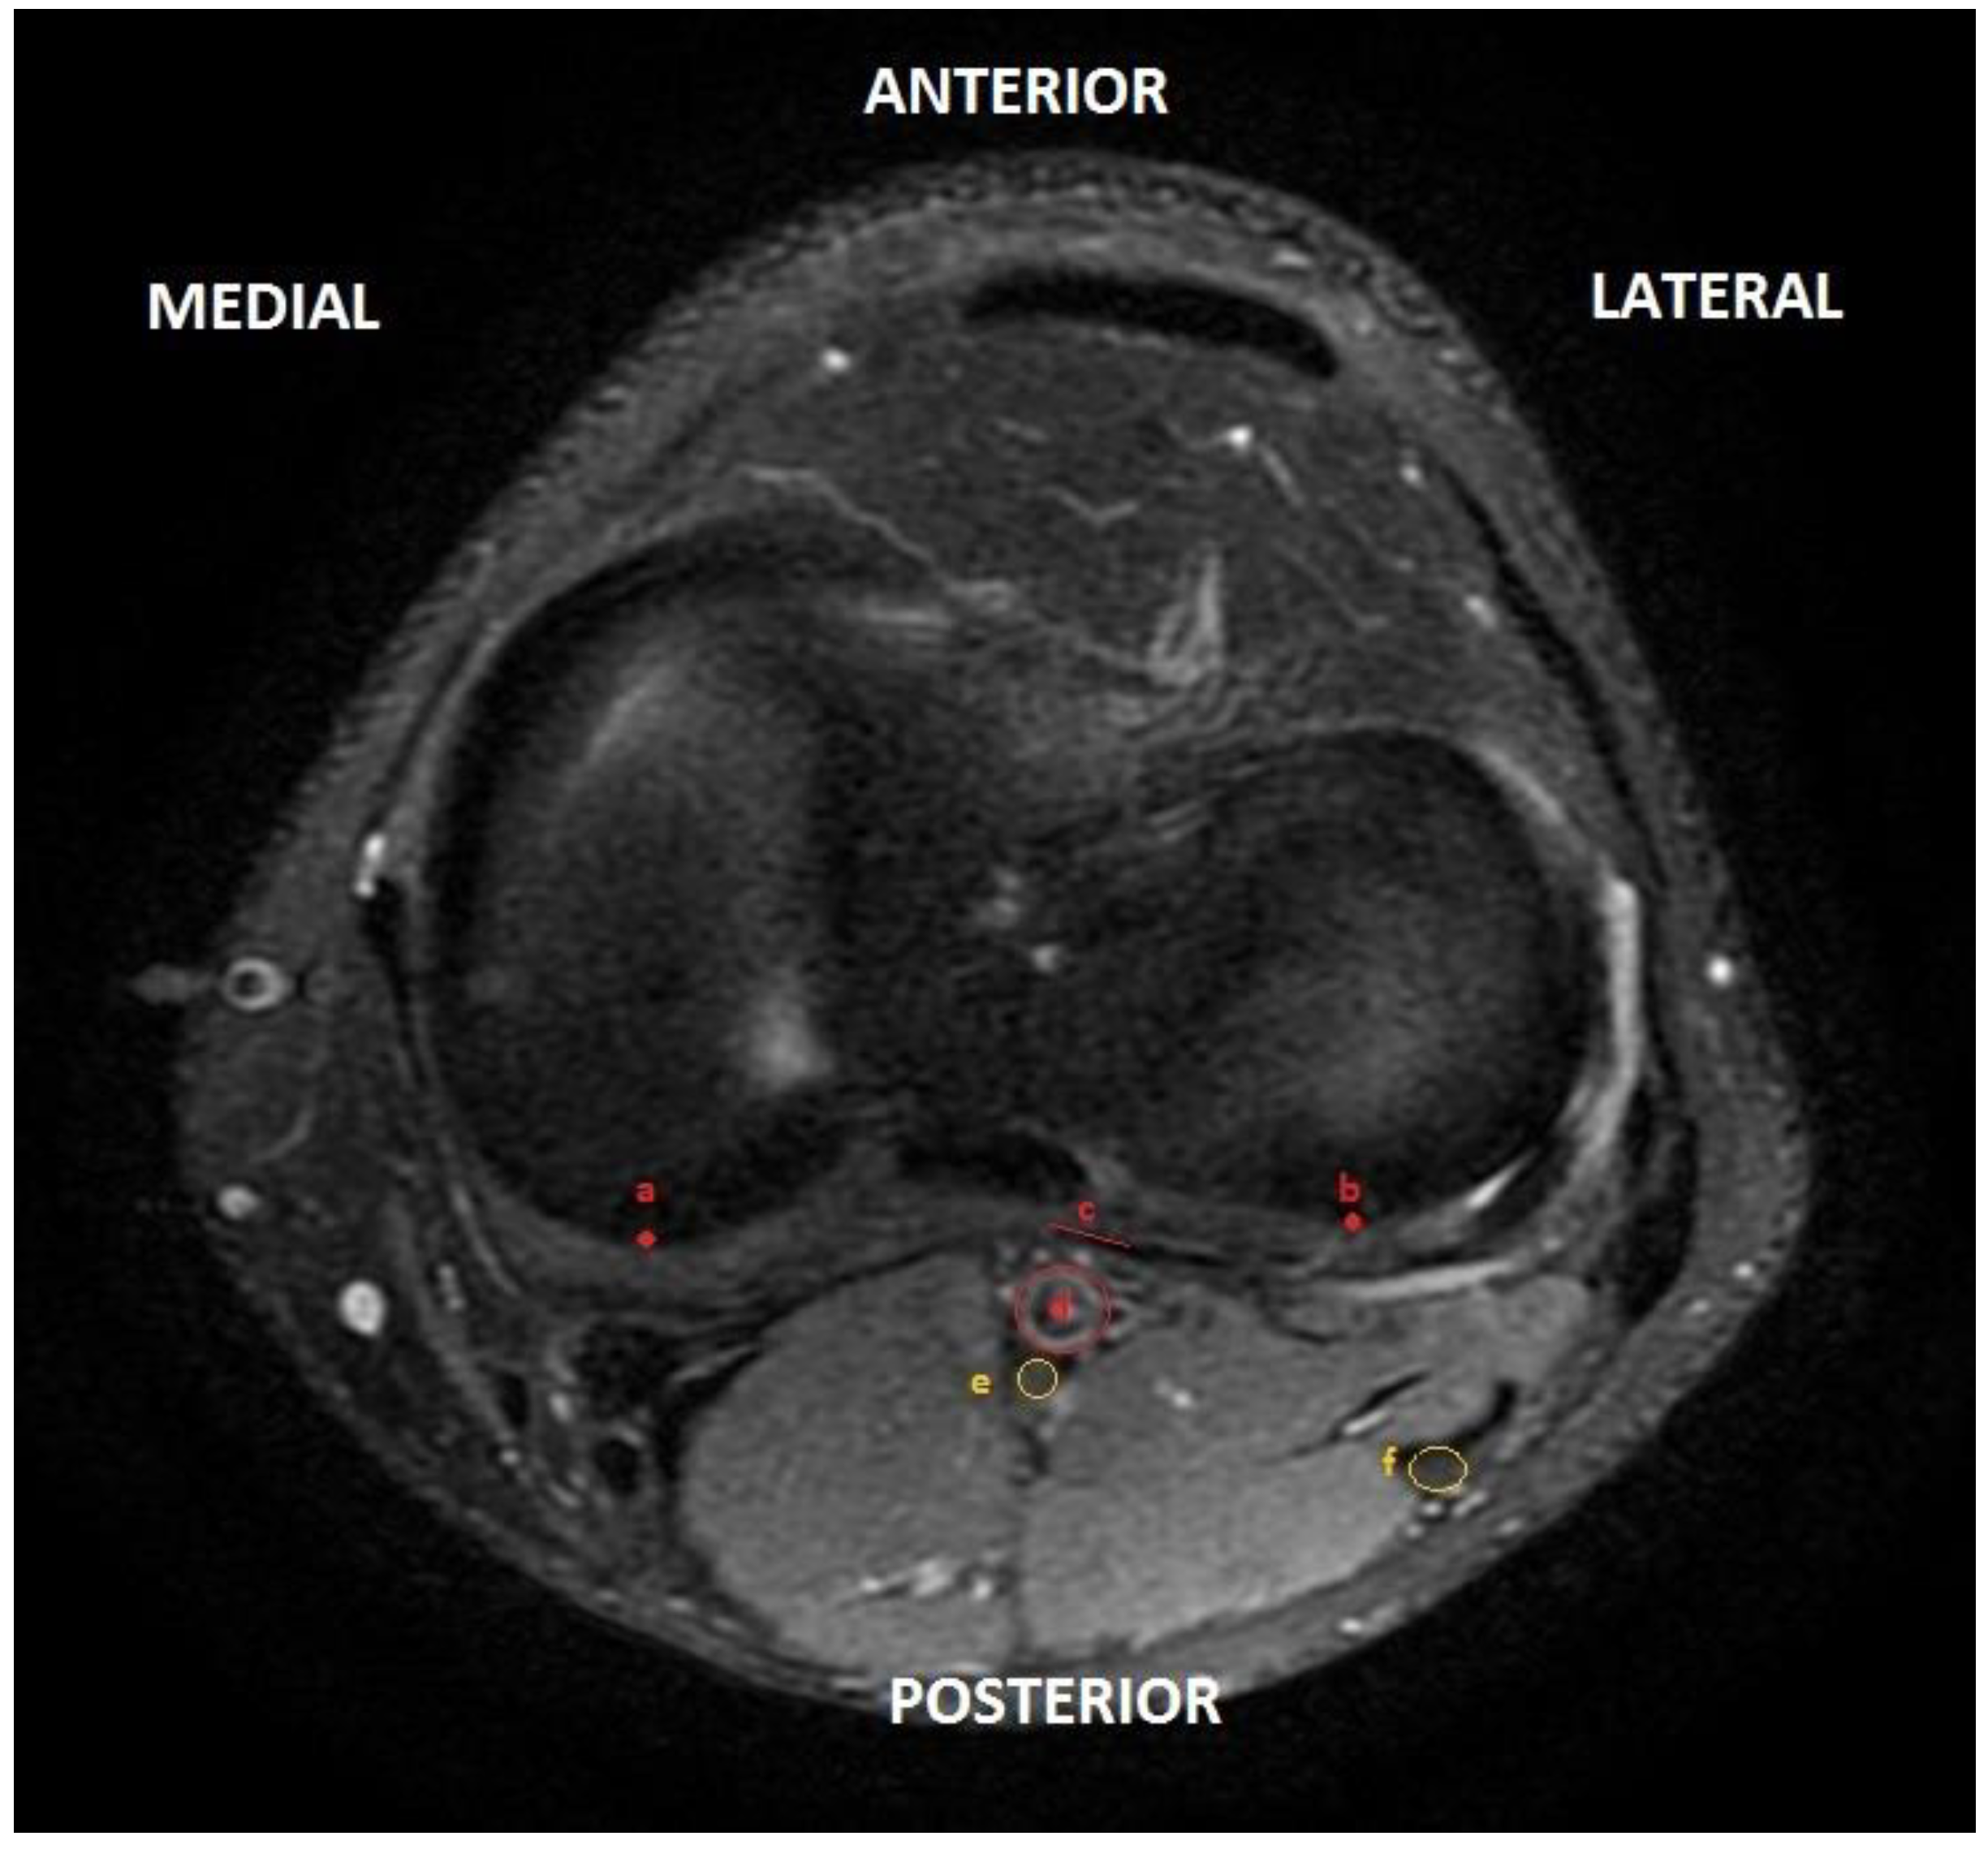

- Distance from the center of the posterior edge of the external tibial plateau to the common peroneal or external popliteal sciatic nerve (EP–EPS);

- Distance from the center of the posterior edge of the external tibial plateau to the internal popliteal sciatic nerve (EP–IPS);

- Distance between common and tibial peroneal nerve (external and internal popliteal sciatic nerve) (EPS–IPS);

- Distance from central posterior capsule to popliteal artery (PC–PA);

- Distance from the center of the posterior border of the internal tibial plateau to the popliteal artery (IP–PA).

- Distance from the intercondylar midline to the center of the popliteal artery (IM–PA). To perform this measurement, the line perpendicular to the coronal axis of both tibial plateaus was drawn at 90° and the distance from the center of the popliteal artery to this line was measured (Figure 3).